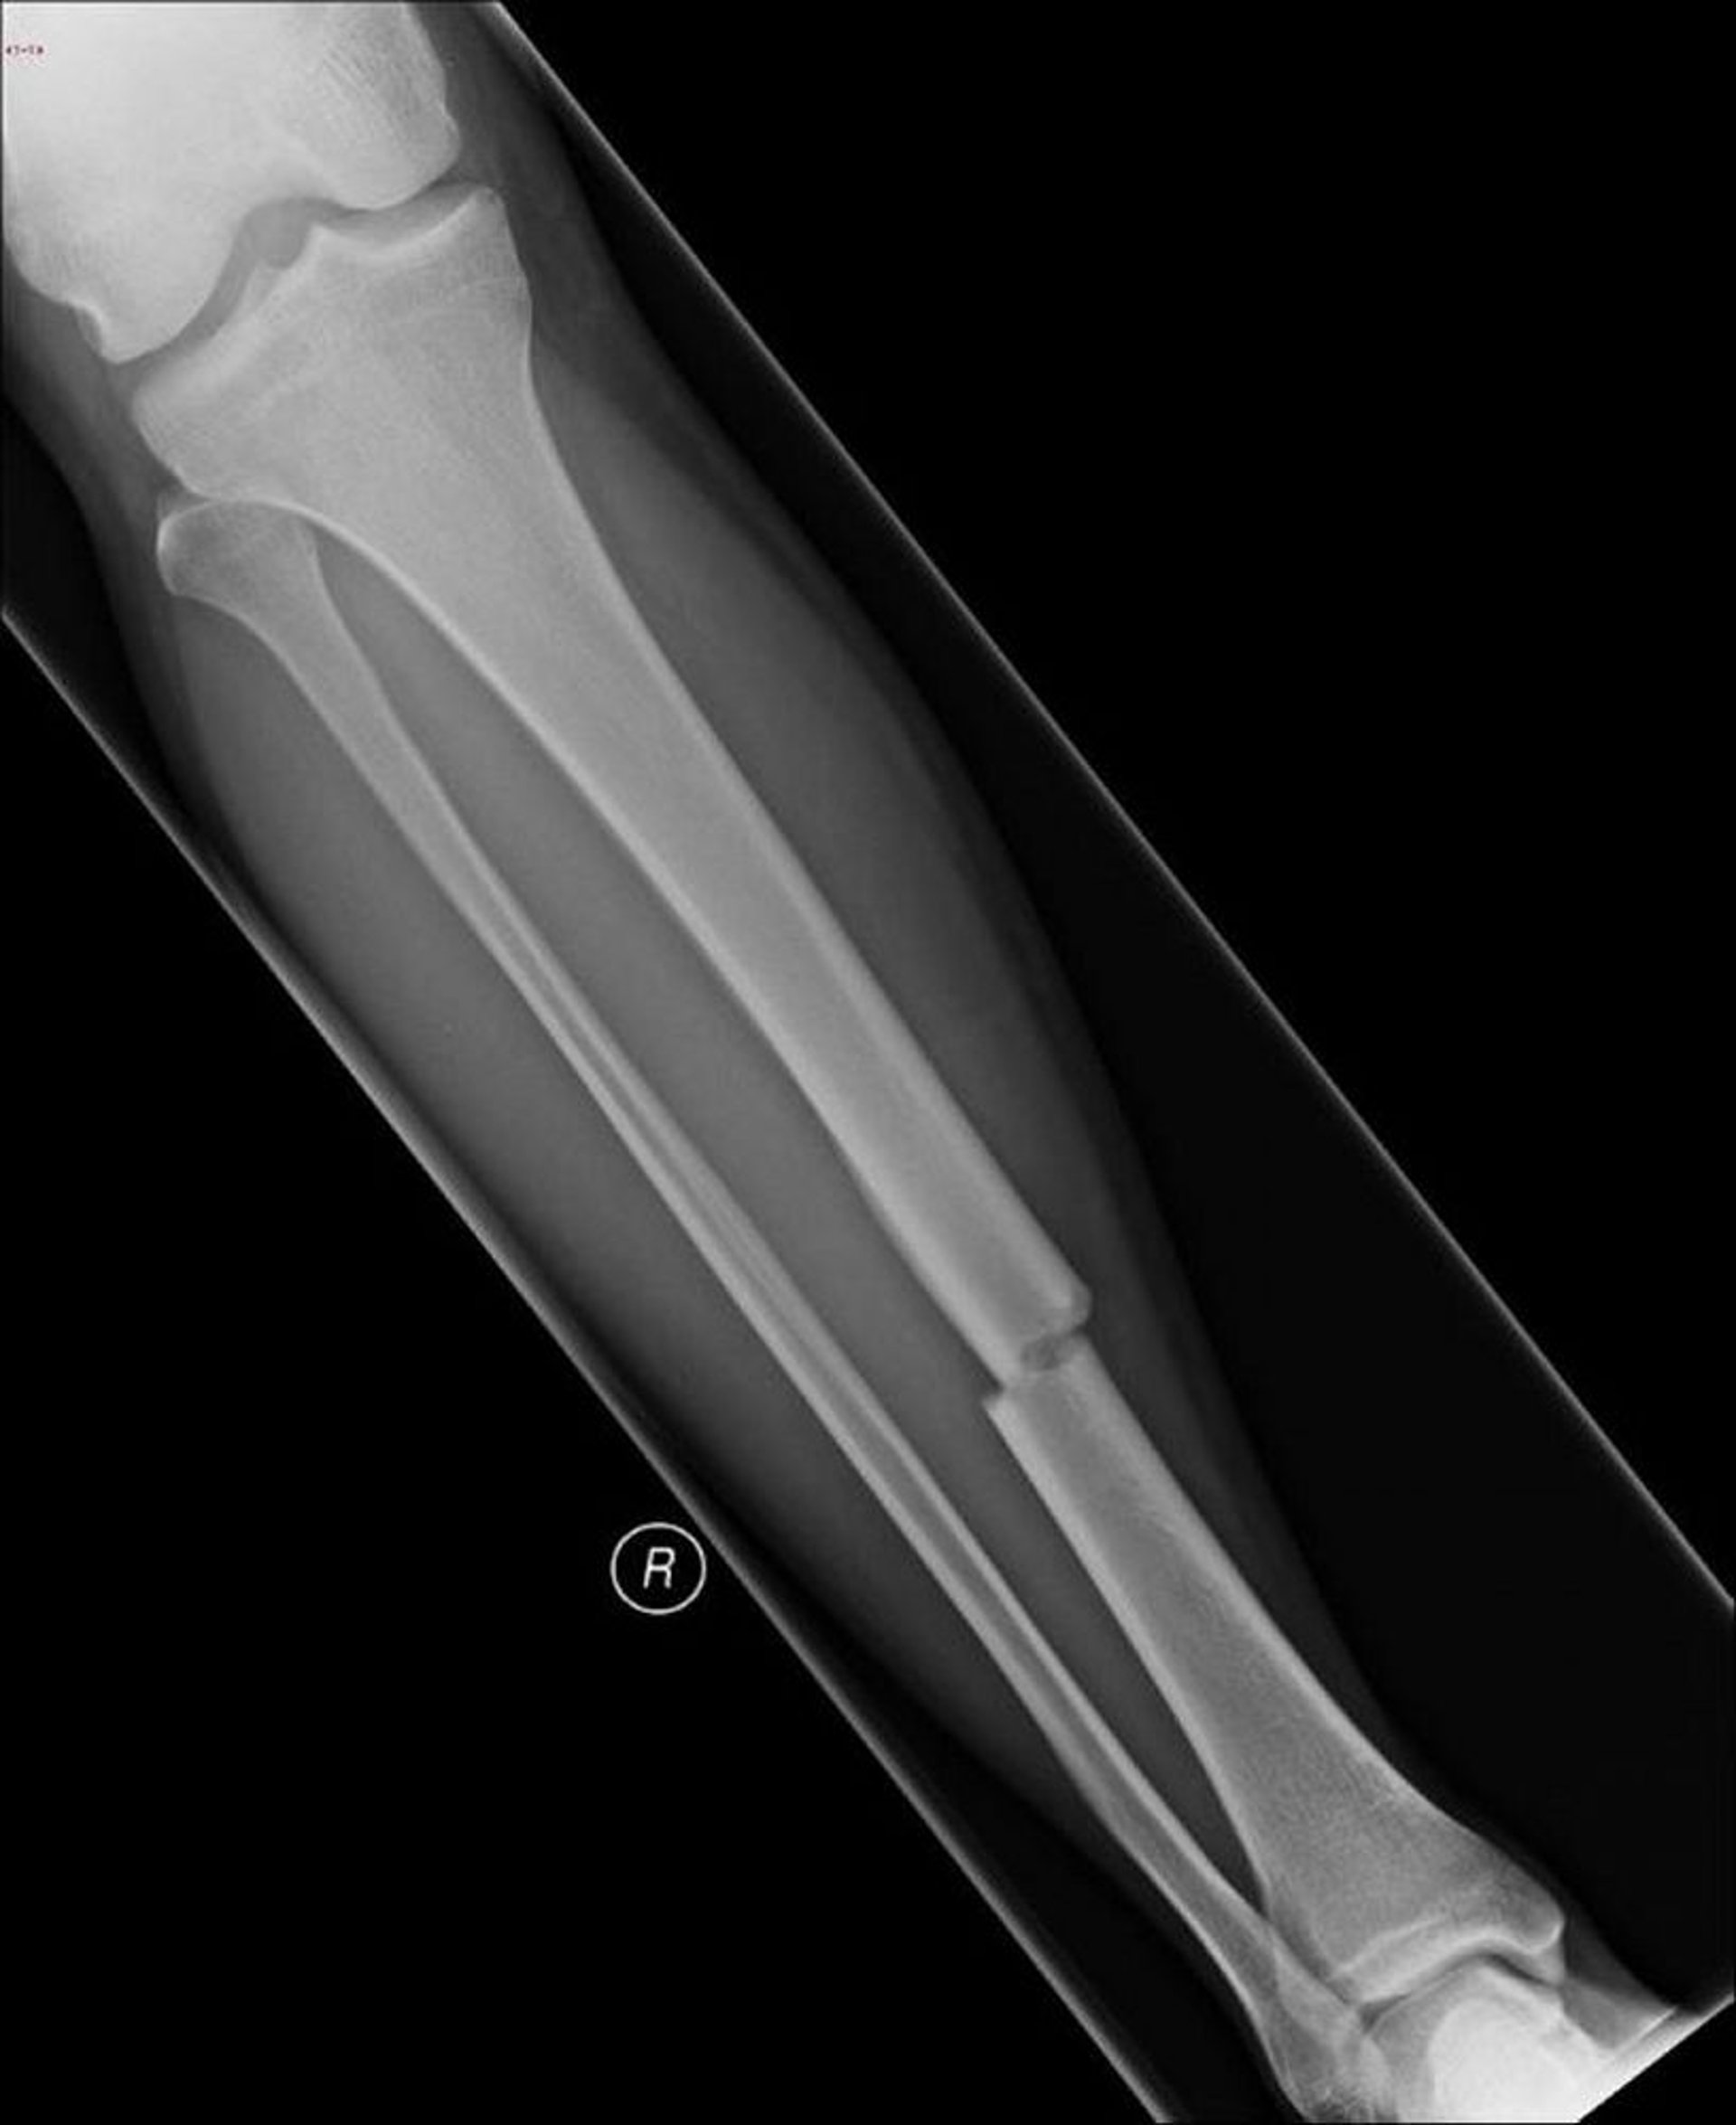

Gãy ngang thân xương chày

Gãy ngang này ảnh hưởng đến trục giữa của xương chày.

Hình ảnh do bác sĩ Danielle Campagne cung cấp.